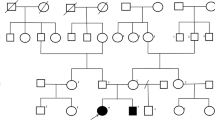

The patient is the only child of healthy nonconsanguineous parents without personal or familial medical history. She was born at 40 weeks of gestation by cesarean delivery without complications. Her birth weight was 3200 g. She had no significant perinatal and postnatal problems. During the first month, she developed infantile spasms that required hospital admission. She was treated with levetiracetam and steroid showed slight improvement. She was noticed that she had low vision and was unable to follow objects. She experienced surgery left inguinal hernia repair at age of 4 months. She had recurrent upper respiratory infection and septicopyemia. She was first seen in the Precision Medical Clinic at age of 1 year. She had dysmorphic features, poor interaction, developmental delay, hypotonia, and low vision (Table 1). Dysmorphic features included full moon face, narrow forehead, small palpebral fissure, broad nose, and generalized edema (Fig. 1a). She was unable to raise her head steadily and roll over. She did not show interest in strangers or surroundings. She was extensively investigated by blood biochemistry examinations, chromosomal microarray, whole exome sequencing, echocardiography, electroencephalogram, and brain MRI. At the age of 4 years, she was unable to sit and turn over, and she seldom got viral or bacterial infection. This study has been approved by the institutional review board of Wuhan Children’s Hospital, Tongji Medical College, Huazhong University of Science & Technology.

a Abnormal facial appearance; b hypoplasia of the corpus callosum and slightly wide sulci at bilateral frontal parietal lobes in brain MRI; c Sanger sequencing of MOGS mutations in the family in our study; d Conservation analysis of MOGS protein among different species. The position of the mutations at amino acids 540 and 565 is indicated by a blue bar and highly conserved throughout all indicated species; eMOGS RNA level was lower in peripheral blood of the patient compared with that of normal control. Both wide-type and mutated MOGS were expressed in Hela cells, and the mutant MOGS expression decreased, RNA level f, protein level g. P: patient, N, normal controls; WT, wild type. The results of three independent experiments are expressed as the mean + standard deviation (*P < 0.05; **P < 0.01)

Blood biochemistry examinations showed abnormal liver function with 55 U/L of glutamic-oxaloacetic transaminase (reference, 10~44 U/L), abnormal myocardial function with 255 U/L of CK (reference, 20~250 U/L), and 68 U/L of CK-MB (0~25 U/L), low immunoglobulin (13.7 g/L; reference, 20~40 g/L), impaired lipid metabolism with decreased HDL (0.75 mmol/L; reference, 0.9~1.74 mmol/L) and ApoA1(0.92 g/L; reference, 1.1~1.95 g/L), increased urine acid (562.7umol/L; reference, 90~420 μml/L). Blood sugar and thyroid function were normal. Echocardiography showed patent foramen ovale or atrial septal defect, electroencephalogram indicated atypic hypsarrhythmia. Brain MRI displayed thin corpus callosum and slightly wide sulci at bilateral frontal parietal lobes (Fig. 1b).

Chromosomal microarray assay and WES analysis

Chromosomal microarray assay did not detect any microdeletion/microduplication in chromosomes. Further, WES and subsequent data analysis revealed two heterozygous mutations (c.1694G>A: R565Q and c.1619G>A:R540H) in exon 4 of MOGS (NM_006302.2) in the patient, and Sanger sequencing confirmed these two mutations in the patient and found that the parents were heterozygous for one of the each mutated alleles (Fig. 1C). These two variants is absent from the variation database (i.e., gnomAD, ClinVar, and 1000 genomes). Bioinformatic analysis showed that sites are conserved among different species (Fig. 1D) and the amino acid substitutions probably damaging, with a high score of PolyPhen-2 server (= 1) and a SIFT tolerance index of 0.0 and 0.003.